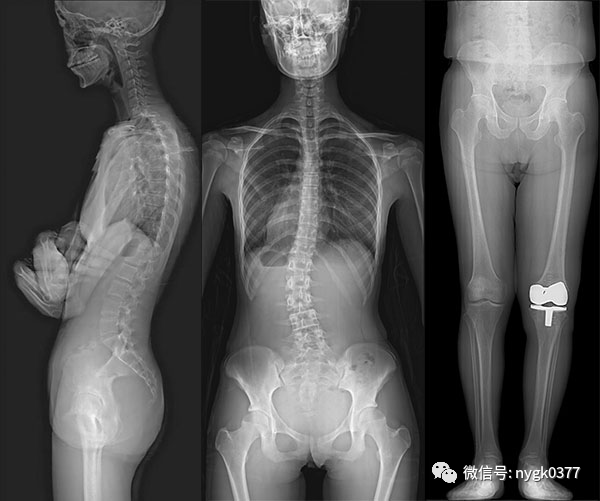

06、狭缝拼接摄影功能

岛津公司首创的狭缝拼接摄影功能,是目前全长摄影中精度高、摄影速度快,可进行立位拍摄和卧位拍摄。采集长度达到142cm,可在12s内完成采集。在全景摄影中起到标准作用,深得广大用户的好评。在脊柱侧弯检查,关节置换测量中起到非常重要的作用。

岛津SONIALVISION 系列RF首创的狭缝拼接摄影功能。

SONIALVISION 系列RF的狭缝扫描拼接摄影功能,使用锥形X射线精确度最高的中心X射线,进行快速的扫描成像。

同时可完成立位及卧位不同需求的狭缝拼接扫描工作。